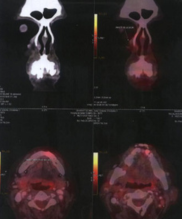

Ewing’s Sarcoma

INITIAL STAGE

10-Feb-2009

Before Treatment :

Scan findings consistent with multiple skeletal mets from Ewing’s Sarcoma.

X-Ray DURING HERBAL ONCOLOGY

01-Aug-2009

Absence of viable tumour

X-RAY AFTER HERBAL ONCOLOGY

04-Sep-2009

AfterTreatment :

No Focus abnormally increased FDG uptake to suggest metabolically active disease on the present study